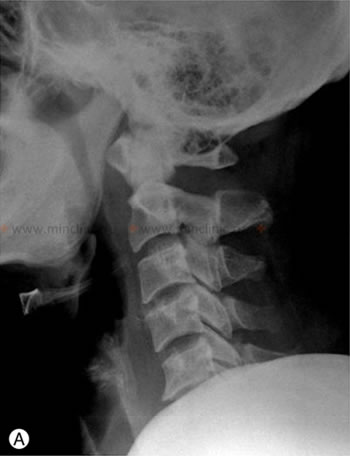

ხერხემლის სვეტის კისრის რენტგენოგრაფიის დროს (გვერდით პროექციაში) ვერ ხერხდება ტრავმის შემდეგ მალების სხეულის გადანაცვლების დანახვა, რადგან ამას ხელს უშლის პაციენტის მხრები.

მალების ამოვარდნილობა იშვიათი მოვლენაა. უფრო ხშირია მათი მოტეხილობები, ხოლო ამოვარდნილობები მათი შედეგია. სუფთა სახის ამოვარდნილობები თითქმის ყოველთვის გვხვდება კისრის მალების მიდამოში. ამოვარდნილ ნაწილად ითვლება ზედა მალა. არსებობს მალების ფლექსიური და როტაციული ამოვარდნილობები. მალების რკალების მიახლოებისას ზედმეტად გაშლას წინააღმდეგობა ხვდება, რაც ამოვარდნილობას ხელს უშლის. თავის მეტისმეტად დახრას მკერდისაკენ შეუძლია გადაადგილოს ზედა მალის სასახსრე მორჩები ქვედასთან მიმართებით (არასრული ამოვარდნილობა, ქვეამოვარდნილობა). ხერხემლის შემდგომი გამართვისას ზედა მალის სასახსრე ზედაპირები შეიძლება წინ გადაცურდნენ და ქვედა მალის სასახსრე მორჩების წინ შედგნენ (სრული ამოვარდნილობა). ამ შემთხვევაში თავი მოქმედებს, როგორც ბერკეტის ძალა, რომლის საყრდენია ქვევით მდებარე მალის ორივე სასახსრე ზედაპირის წინა მხარეები. ამიტომ კისრის ფლექსიური ამოვარდნილობა ყოველთვის ორმხრივია.

კისრის ტრავმის დროს მეტისმეტად მოხრას ან გაშლას შეუძლია გადაადგილოს კისრის მალები და გამოიწვიოს ამოვარდნილობა.